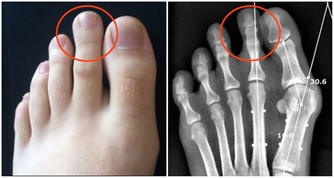

2、水皰為位於表皮深處的小水皰,米粒大小,半球形,略高於皮表,分散或成群發生在手上;

3、內含清澈漿液,發亮,偶爾可變渾濁;

4、小水泡多不自行破裂,破裂后可見圓領狀脫皮;